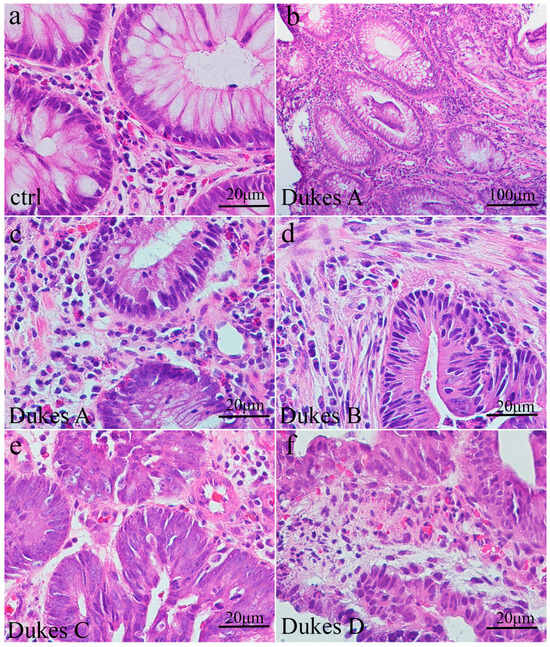

Analysis of healthy colon tissue revealed specific structural features visualized by hematoxylin and eosin staining. Goblet cells, specialized for mucus secretion, were abundant in the epithelium that lines the inner surface of the colonic crypts (glands); these appear as clear, rounded spaces (Figure 1a). The lamina propria, a layer of connective tissue supporting the epithelium, was inter-spread between the crypts. The nuclei of columnar and goblet cells were located at the basal ends of the cells and presented with a dark purple color.

In colorectal cancer (Dukes A and B), staining reveals partially preserved crypt architecture with irregular crypt formations. Goblet cells were reduced in number, and epithelial cells exhibited nuclear abnormalities (Figure 1b–d). The section of human Dukes C and D demonstrated necrotic debris within the lumen of adenocarcinomatous glands, replaced by disorganized, malignant growth (Figure 1e,f).

Figure 1. The morphology of intestinal crypts is altered in colorectal cancer tissue compared to healthy tissue. Section of healthy adult colon (a) with circular crypts and basally positioned nuclei within cells with underlying lamina propria; section of Dukes A human colon cancer (b,c) with moderately formed crypts lined by epithelial cells with impaired nuclear position; section of Dukes B human colon cancer (d) with the cellular debris within gland lumen; section of Dukes C and D (e,f) human colon with disrupted glands underlined by atypical epithelial cells.